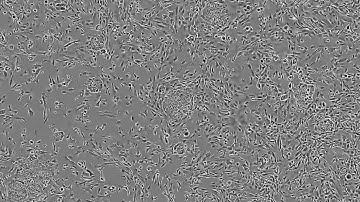

Reprogramming Skin Fibroblasts to hiPSCs